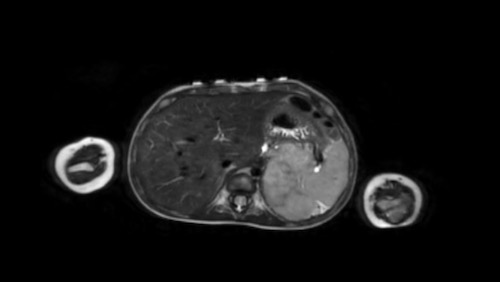

Hình ảnh

Hình ảnh MRI của một bé gái chín tháng tuổi có khối u ở bụng trái. MRI cho thấy khối u tuyến thượng thận trái, một phần đặc, một phần nang. Có nhiều di căn gan.

Khối u đã được sinh thiết. Có tình trạng chảy máu liên tục qua kim dẫn đường. Vào cuối thủ thuật, hai nút bọt gelatin đã được đặt vào (các dải tăng âm (mũi tên)).